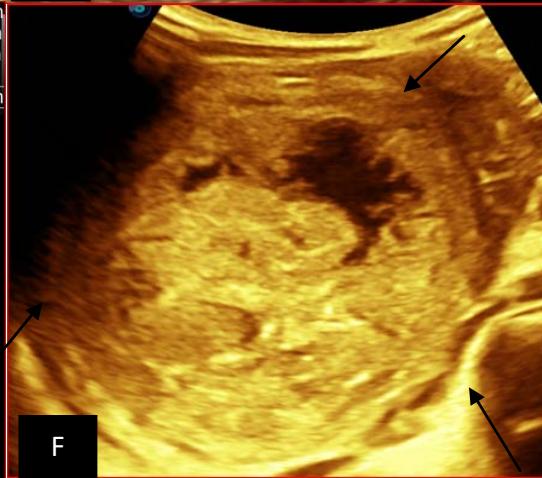

Figure 5: Abdominopelvic ultrasound control after 6 courses of chemotherapy in the same 3 year old patient with a ruptured left renal nephroblastoma; Images A, F, G, and H: show regression of the solid, endo and exo renal, left nephroblastoma mass treated with 6 courses of chemotherapy (current volume 430 ml vs) Images: B, C, and: show persistence of thrombotic permeation pan vena cava and ipsilateral renal. Image E: shows a volumetric regression of the intra-lesional hematic collection, at the tumor rupture estimated at 34.49 ml VS, Image I: represents the right kidney in B mode which is of normal echoculture. Source: Dr. Frederick Tshibasu Tshienda database.